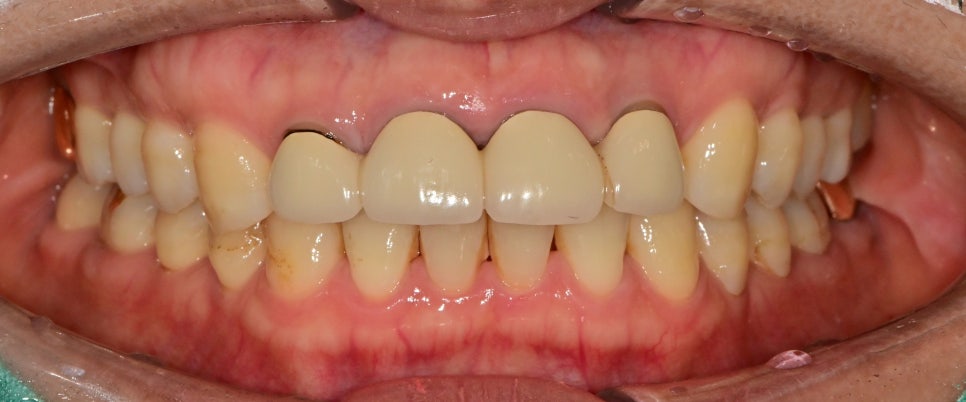

구강 내 사진만 보았을 때는

일단 치아 길이가 너무 짧아 비율적으로 심미적이지 않고

시간이 오래 지남에 따라 잇몸의 수축으로

치아와 보철물 경계가 어둡게 보였습니다.

임시치아 상태에서의 비율, 형태의 평가

기존 치아의 형태가 너무 짧아 비율적으로 안 맞았기 때문에

임시치아 상태에서는 치아 길이를 조금 연장해서 형태를 잡아보았습니다.

아직 임시치아 상태이고 수정을 여러 번 하며 환자분께서는

현상태의 치아 형태가 가장 마음에 들어 하셔서 임시치아의 형태를 참고하여 최종 보철물을 제작하기로 했습니다.